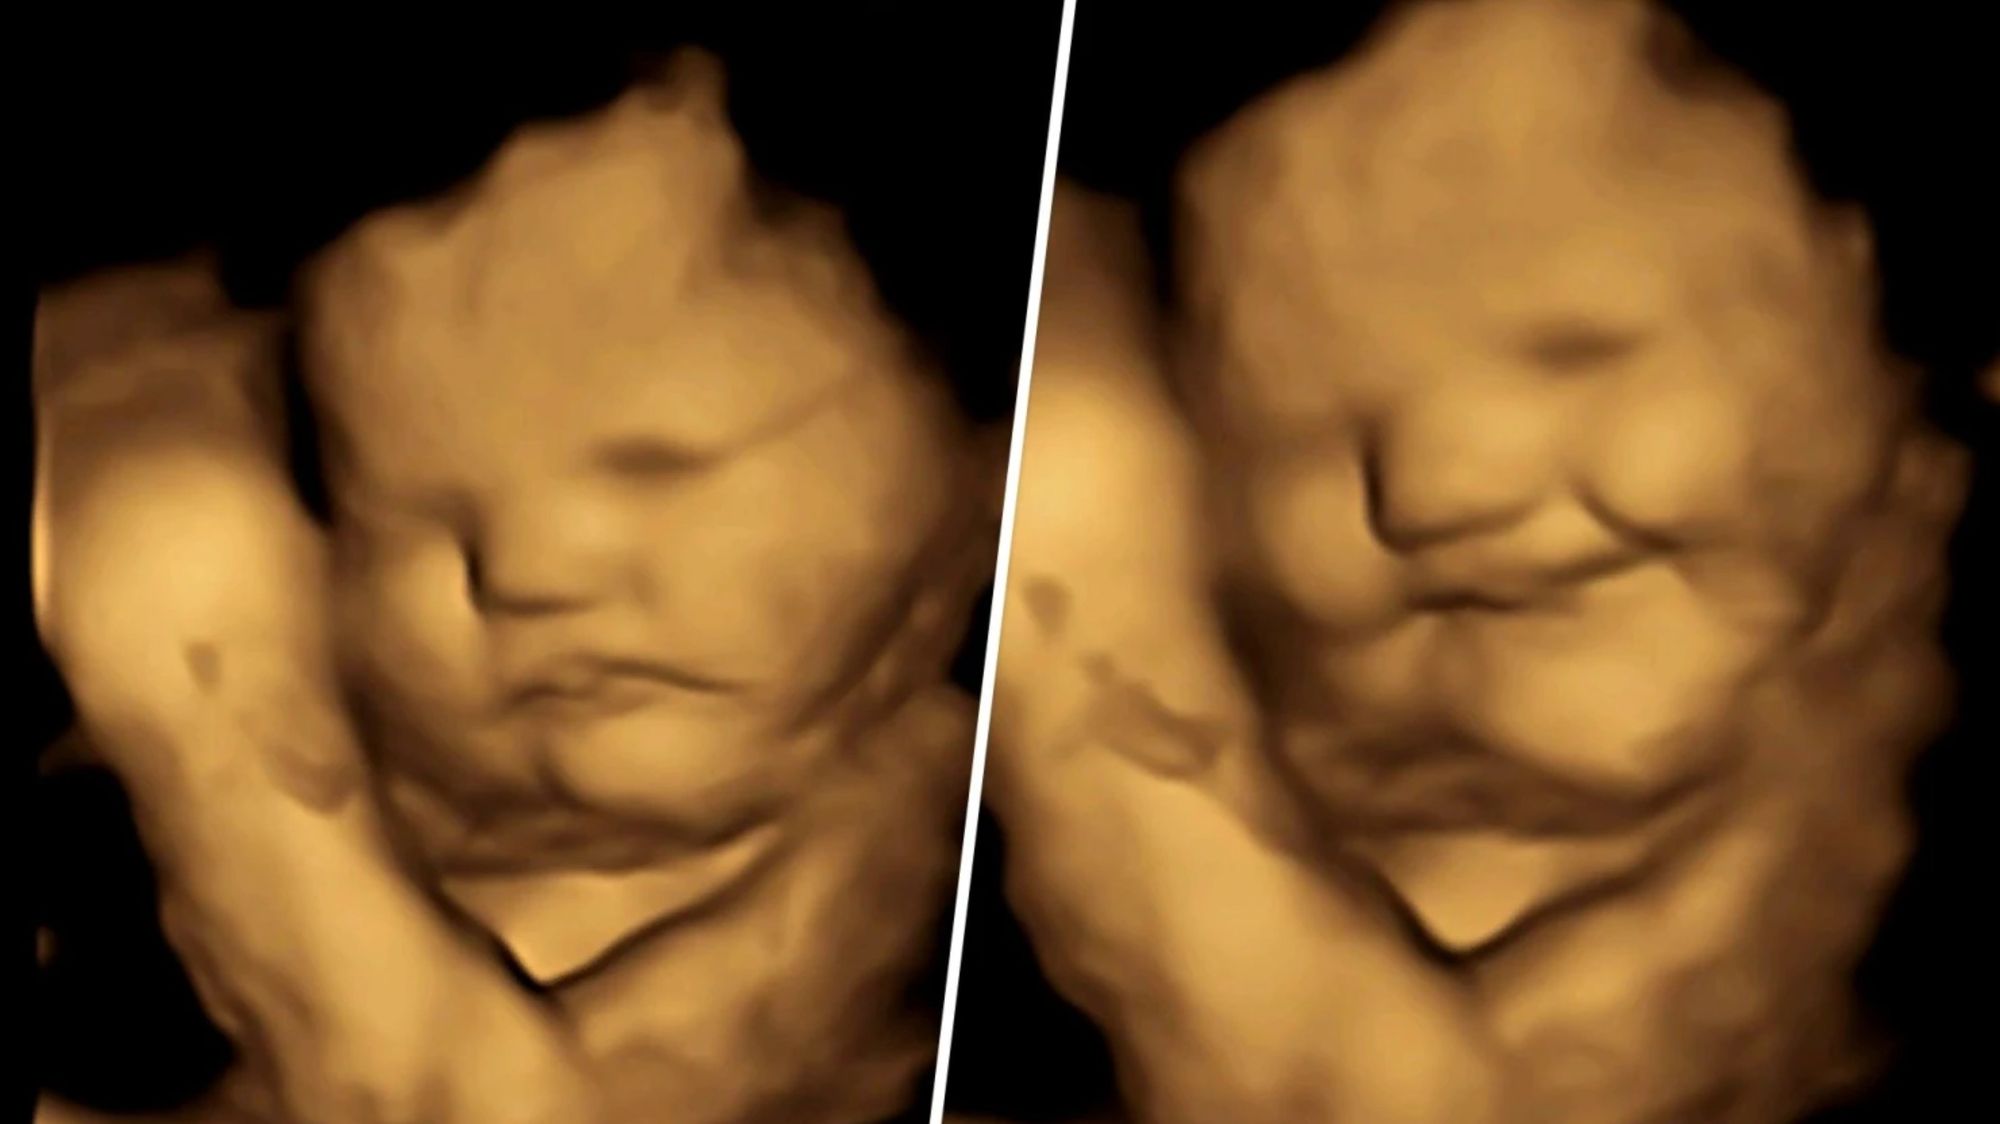

Bilim insanları, anne karnındayken yüz ifadelerine bakarak, bebeklerin çeşitli koku ve tatlara farklı tepki verdiğine dair ilk doğrudan kanıtı kaydetti.

İngiltere'deki Durham Üniversitesi'nin Fetal ve Neonatal Araştırma Laboratuvarı tarafından yürütülen bir araştırma, 100 hamile kadından 4D ultrason taramalarını kullandı.[1] Bununla, doğmamış bebeklerin anneleri tarafından yenilen yiyeceklerin lezzetlerine maruz kaldıktan sonra nasıl tepki verdiklerini görmek amaçlandı.

Araştırmacılar, anneler havuç ve lahana aromalarını yedikten kısa bir süre sonra fetüslerin bu aromalara nasıl tepki verdiğine baktılar. Havuca maruz kalan fetüsler daha fazla "kahkaha yüzü" tepkisi gösterirken, lahanaya maruz kalanlar daha fazla "ağlama yüzü" tepkisi gösterdi.

Her iki lezzet grubunda da görülen yüz reaksiyonları, her iki lezzete de maruz kalmayan bir kontrol grubundaki fetüslerle karşılaştırıldı. Bunun sonucunda, çok az miktarda havuç ya da lahana aromasına maruz kalmanın, bir reaksiyonu canlandırmak için yeterli olduğu ortaya çıktı.